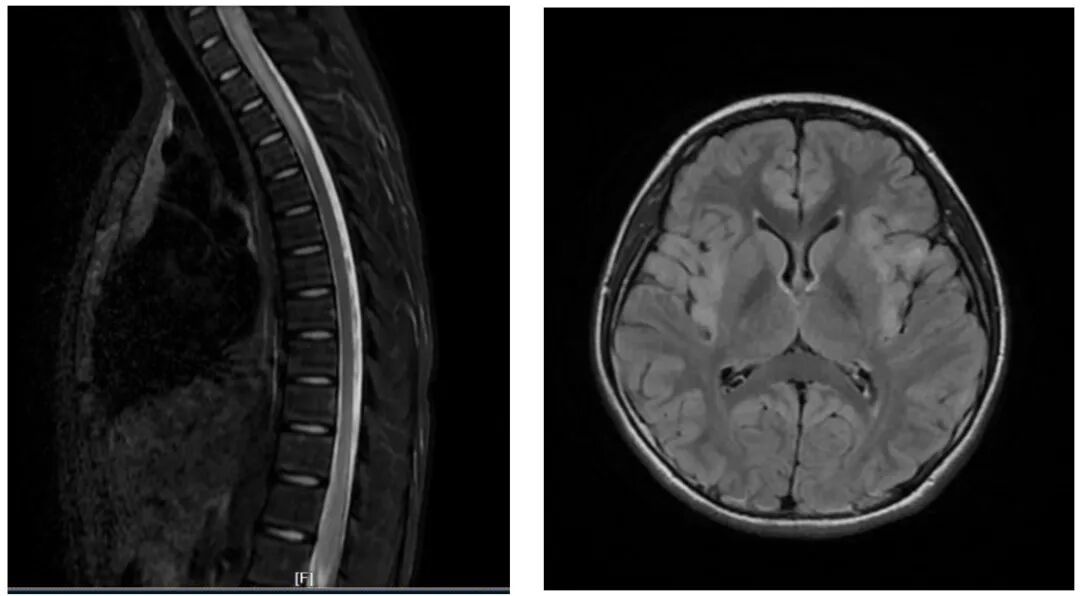

神经内科专家经详细问诊、查体后,当即决定将双双收入院,并安排了血液检查、腰椎穿刺、头颅 + 全脊髓磁共振等一系列检查。最终明确诊断,双双患有中枢神经系统脱髓鞘病。

双双的病情属于起病急、进展快、病情重的类型,若不及时干预,很可能危及生命并留下终身后遗症。明确诊断后,神经内科团队立即启动治疗。经过积极救治,双双的肢体麻木症状已完全消失,肢体无力明显好转,目前已能短距离独立行走,正在逐步康复中。